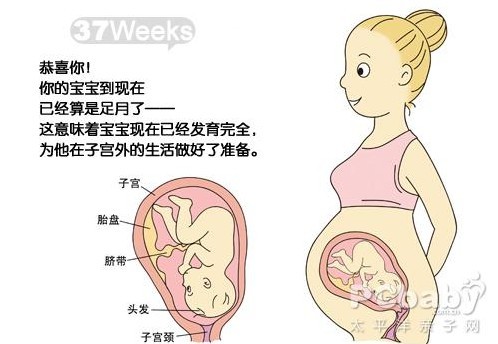

怀孕9个月妊娠9个月,胎宝宝已经发育得足够大了,如果按照我们日常生活计算的9个月,此时胎宝宝随时都有发动的可能。当然了,由于这个阶段的胎宝宝已经足够“丰满”,因此准妈妈在B超上看到的胎宝宝其舌头和鼻子都显得特别大,如果不仔细看,可能根本分辨不出来。

怀孕1~9个月宝宝的B超图分开来看,可能并不太直观,但如果把这些都拼在一起,准妈妈就可以看到胎宝宝逐渐发育成长的样子。是不是感觉很神奇呢?

最后要说的是:宝宝的发育是一个不断变化着的动态的过程,为了生出一个健康的宝宝,准妈妈可一定要记得按时产检哦。